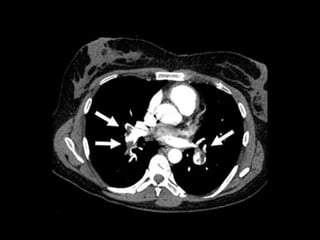

• #62 Spiral-CT des Thorax nach intravenöser Kontrastmittelgabe. Pneumomediastinum (Pfeil) und linksseitiger Pleuraerguss (*)